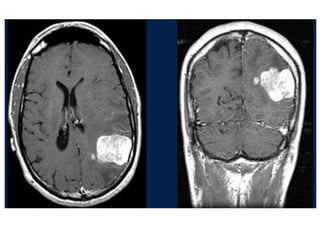

 6% al23% del total de pacientes con CA diferenciado, desarrollan metástasis a distancia.  1% al 4% son evidentes al momento del diagnóstico.  Pacientes con mets a distancia tienen una sobrevida a 5 años del 50%.  El sitio más frecuente es el pulmón, seguidos de hueso, menos frecuentes, cerebro, hígado y piel.  Factores que predicen un peor pronóstico son:  Síntomas, edad >45 años, y poco captación de yodo.

 En lasmets pulmonares algunos factores que mejor el pronostico son: paciente joven, tumor pequeño y sensible al yodo.  El tratamiento con yodo es mas efectivo en las mets a pulmón que en hueso.  Las mets a hueso son más comunes a en el CFT (vértebras, pelvis y costillas son los sitios más afectados).  Considerar cirugía o radioterapia si existen síntomas.  Las mets a cerebro son raras no hay consenso si es mejor el tratamiento de éstas.